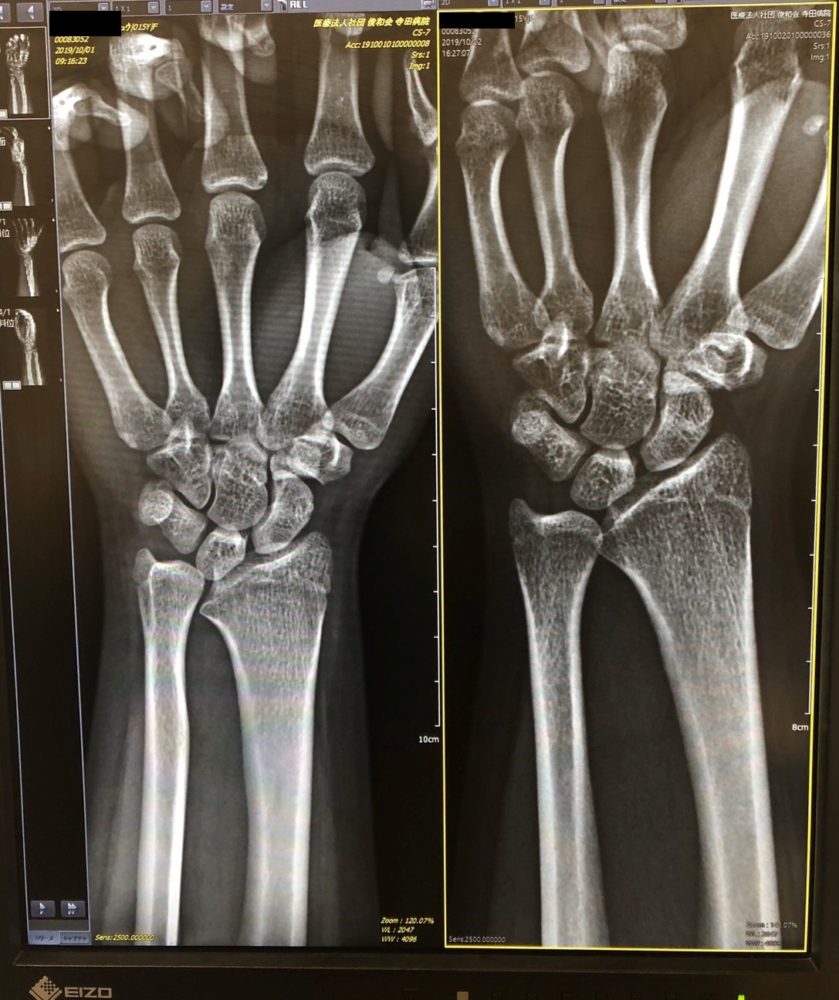

TFCC損傷尺骨突き上げ症候群druj不安定症入院手術尺骨短縮術ギプス手術跡レントゲン入院記録抜釘手術。

TFCC損傷・尺骨短縮術 術後2年 リハビリも続き現状の手首の状態は・漁師の徒然なるブログ。

術後8ヶ月 TFCC損傷漁師の徒然なるブログ。

TFCC損傷・尺骨短縮術 入院~手術~術漁師の徒然なるブログ。